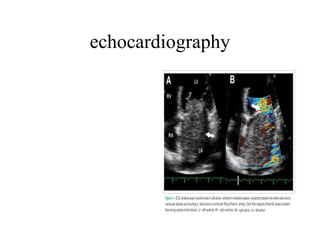

echocardiography There are two major types of echocardiography: M-mode (below left) and two-dimensional (below right) (Fig. 2, [3])

echocardiography In the M-mode a single beam of ultrasound is used (Fig. 3, [3]) The reflections of the signal are recorded and displayed as monochronic dots. The location is proportional to the distance from the reflective region, and the intensity contains the information about acoustic impedance of the region. The M-mode has excellent axial resolution, but it carries essentially one-dimensional information. The two-dimensional echocardiograph typically uses a multielement transducer, which generates a single ultrasonic beam with changing direction. This technique allows one to create a two-dimensional image, which has good lateral resolution but lacks accuracy in the axial dimension.

echocrdiography Examples of two-dimensional still frames obtained from hand-held echocardiographic examinations of four distinct patients.  (A)  Parasternal long axis view obtained from a patient admitted for septic shock secondary to a severe aortic endocarditis (arrows indicate vegetations) associated with a massive regurgitation and dilated left ventricle.  (B)  Parasternal short axis view obtained from a patient with an acute respiratory distress syndrome and associated cor pulmonale. The right ventricle was markedly enlarged and the ventricular septum bulged towards the left ventricular cavity at end systole, due to severe pulmonary hypertension (arrow).  (C)  Apical four-chamber view obtained from a ventilated patient with refractory hypoxemia. The contrast study (intravenous injection of saline microbubbles) revealed a large interatrial right-to-left shunt through a patent foramen ovale, which participated to persistent hypoxemia: left cardiac cavities were filled up by the microbubbles within two cardiac cycles.  (D)  Subcostal view obtained from a patient presenting with shock and pulsus paradoxus. A mild pericardial effusion responsible for prolonged right atrial collapse during the cardiac cycle (arrow) was consistent with a tamponade, and the patient underwent successful pericardotomy. LV, left ventricle; RV, right ventricle; LA, left atrium; RA, right atrium; Ao, ascending aorta.